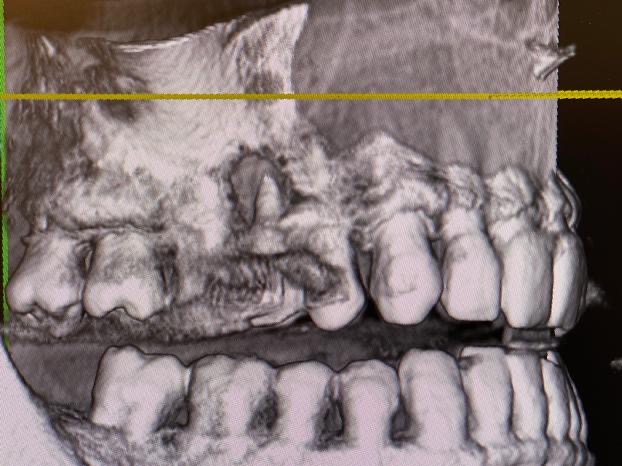

Un leggero fastidio durante la masticazione e un lieve dolore. È quanto accusato da un paziente che presentava una piccola tumefazione gengivale in corrispondenza dell’elemento 1.5.

Dall’esame radiografico effettuato con RVG, tuttavia, non sono emerse lesioni. Molto spesso, infatti, per poter effettuare una diagnosi corretta non è sufficiente affidarsi alla sola immagine radiografica.

È qui che l’utilizzo della ConeBeam offre un quadro più ampio e permette al medico di fornire una diagnosi più rapida.

Dalla radiografia 3D, in questo caso, è emersa una situazione completamente differente. Il paziente presentava una reazione infiammatoria con riassorbimento dell’osso periradicolare, probabilmente di origine traumatica o endodontica.